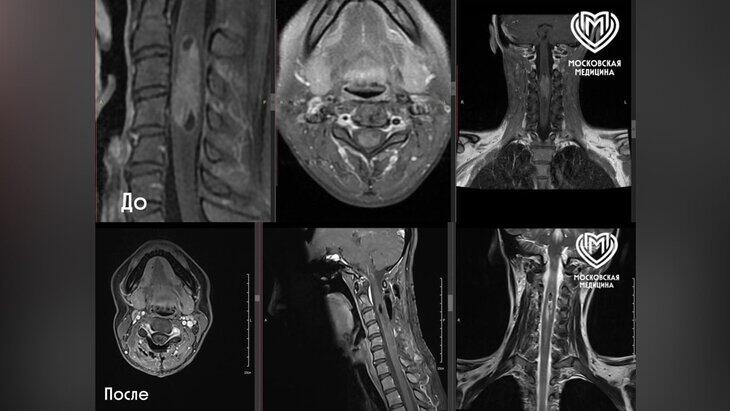

Milli.Az xəbər verir ki, Moskva Səhiyyə Departamentinin məlumatına görə, qadın sağ əlinin orta barmağında uyuşma və yanma hissi şikayəti ilə müraciət edib. Müayinə zamanı həkimlər onun onurğa beyninin C2-C5 səviyyələrində təxminən 6 santimetr uzunluğunda şiş (ependimoma) aşkar ediblər.

Əməliyyat mikroskop altında və neyrofizioloji monitorinq vasitəsilə aparılıb. Bu üsul həkimlərə əməliyyat zamanı sinir keçiriciliyini və həssaslığı nəzarətdə saxlamağa imkan verib. Neyrocərrah Dmitri Vakatov bildirib ki, əməliyyat zamanı MRT və MRT traktoqrafiyası sayəsində sinir yollarının dəqiq xəritəsi hazırlanıb və bu, nevroloji fəsad riskini minimuma endirib.